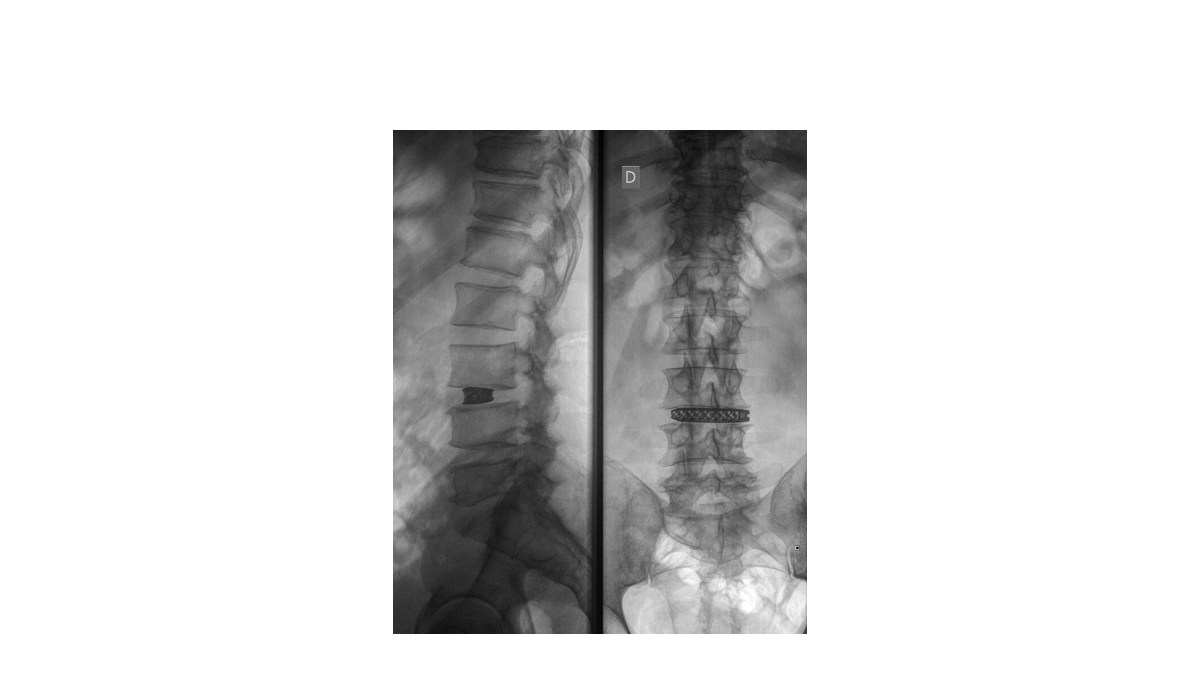

Hitrejše pa je okrevanje pacientov, ki jih operirajo z novimi metodami, ki so manj invazivne. Taka je nova metoda operacije, imenovana XLIF (ang. eXtreme Lateral Lumbar Interbody Fusion), po kateri so lani začeli operirati na ljubljanski ortopedski kliniki. Primerna je za bolnike s kronično mehanično bolečino v križu. Namesto dolge operacije, ob kateri je bolnik močno krvavel, je nova operacija kratka in brez izgube krvi. "To v praksi pomeni manj invaziven poseg in krajši čas rehabilitacije," je poudaril ortoped, ki operacijo izvaja, dr. Lovro Suhodolčan (spodaj fotografije te operacije).